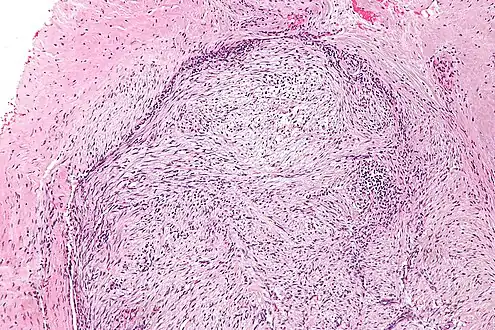

| Micrograph of nodular fasciitis showing the haphazard arrangement of cells (tissue culture-like pattern). H&E stain. | |

The microscopic histopathology of hematoxylin and eosin stained nodular fasciitis tumors (see above and three below figures) consists of spindle-shaped myofibroblastic cells (i.e. cells with features of smooth muscle cells and fibroblasts.).[9] These cells are in a myxoid (i.e. more blue or purple compared to normal connective tissue because of excessive uptake of the hematoxylin stain) or a collagenous (high content of collagen fibers) tissue background. The neoplastic myofibroblasts are arranged in whorls and/or short bundles. These cells may show high rates of replicating as judged by their mitotic index but these mitoses are normal in appearance. The tumor tissues often contain red blood cells, lymphocytes and giant osteoclast-like giant cells and may contain sites of bone-like tissue.[11] NF is sometimes classified into three subtypes based on its predominant histopathological pattern: myxoid or reactive (type I), cellular (type II), and fibrous (type III).[5] These patterns appear related to the duration of the lesion with the myxoid variant tending to have the shortest duration and the cellular and fibrous variants tending to have progressively longer durations.[15]Immunohistochemical analyses indicate that the cells in NF usually express smooth muscle actin, muscle specific actin, and vimentin proteins but generally do not express CD34, S-100 protein, desmin, trypsin, factor VIII, F4/80 (also termed macrophage-specific antigen), or HLA-DR1 proteins.[11] Uncommonly, the cells in NF tumors also express the CD68 (a histiocyte-specific marker) protein.[5]